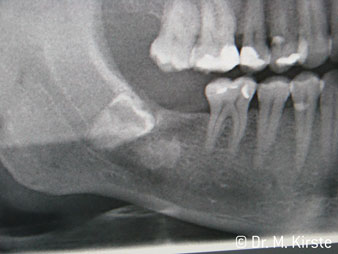

La scelta dell'angolo di 45° del contrangolo offre numerosi vantaggi in sede di utilizzo. I colleghi chirurghi, per i quali è stato messo a punto in primo luogo il contrangolo, noteranno in fretta la possibilità di lavorare in modo molto mirato. In particolare, durante l'estrazione dei denti del giudizio (Fig. 2), non sono necessarie estese resezioni del tessuto molle nell'area della guancia (Fig. 3). La forma della testina del contrangolo, insieme a lievi rotazioni della stessa durante la preparazione, permettono di lavorare in modo rapido e sicuro nella regione retromolare.

Fig. 2